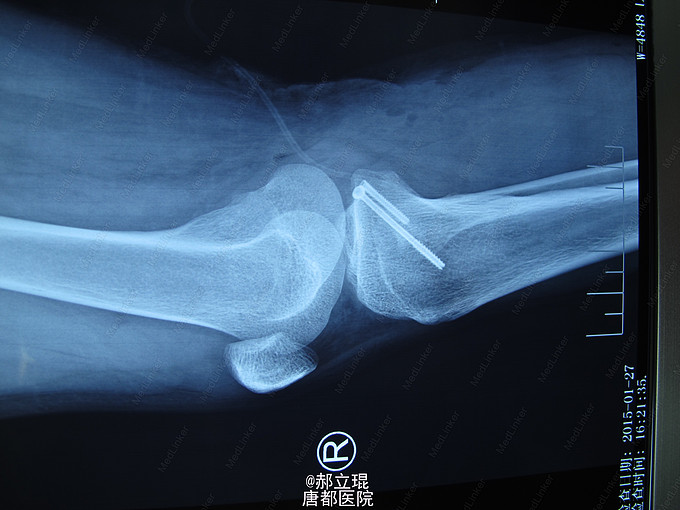

入院后给与影像学检查完善及相关术前准备,于伤后第7天行髁间棘骨折,切开复位内固定术。术后早期功能锻炼。

患者术后6周,膝关节部分负重,3月后完全负重,并膝关节活动功能完全正常。无明显创伤性关节炎的表现。本手术采用后侧入路,于腓肠肌内外侧头间隙入路,手术安全,但要注意血管神经束的保护。术后应早期功能锻炼,同时应用抗凝药物,预防血栓,尤其是腘动脉牵拉造成的血栓。